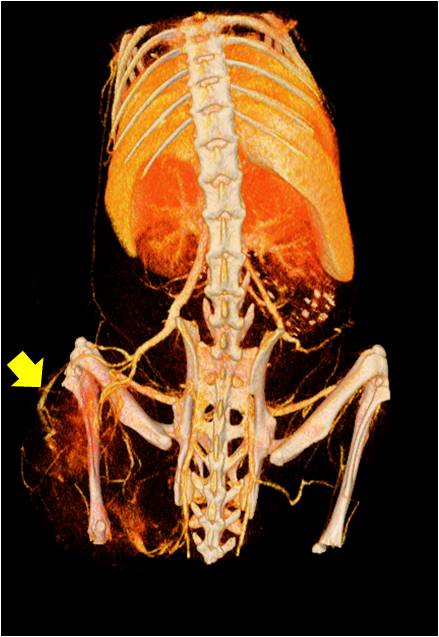

腫瘤血管生成

肺轉(zhuǎn)移

小鼠模式,22.5μm像素

正常

8天 14天

無造影劑注入 造影劑注入